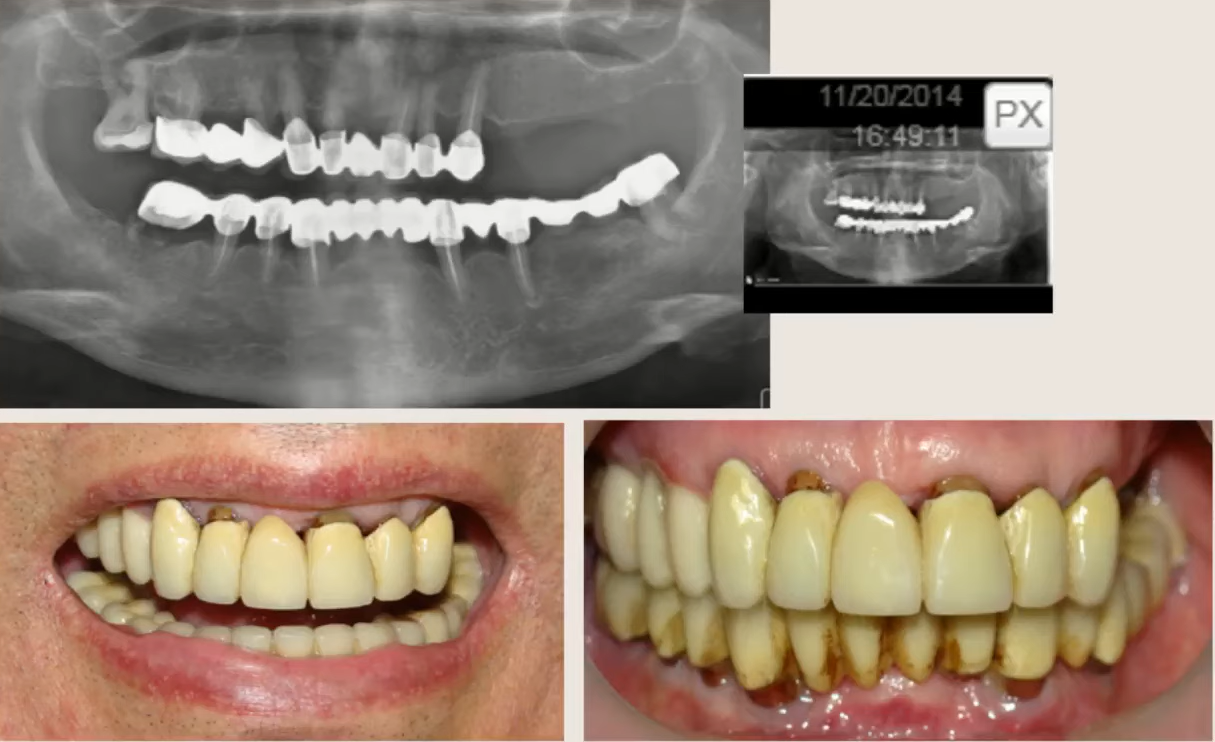

Here’s another clinical example. The patient also expressed a desire to leave after the surgery with her teeth intact. The initial clinical picture was quite dire.

The initial clinical situation: the remaining natural teeth are practically hopeless; both jaws require extraction and prosthetics. YouTube / Dr. Kamil Khabiev / Dental Guru Academy

In this case, we’ll only briefly present the results. The point is that the same principle was adopted here: cancellous implants for the upper jaw and cortical implants for the lower jaw.

The appearance of a temporary denture immediately after placement. YouTube / Dr. Kamil Khabiev / Dental Guru Academy